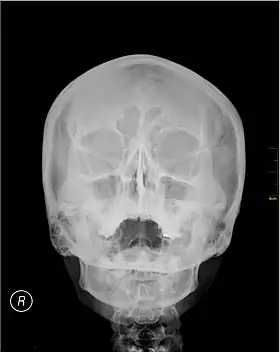

Waters' view

Waters' view (also known as the occipitomental view) is a radiographic view of the skull. It is commonly used to get a better view of the maxillary sinuses. An x-ray beam is angled at 45° to the orbitomeatal line. The rays pass from behind the head and are perpendicular to the radiographic plate. Another variation of the waters places the orbitomeatal line at a 37° angle to the image receptor. It is named after the American radiologist Charles Alexander Waters.

![]() A Waters' view radiograph showing the paranasal sinuses | |

Uses

Structures observed

Waters' view can be used to best visualise a number of structures in the skull.

- Maxillary sinuses.

- Frontal sinuses, seen with an oblique view.

- Ethmoidal cells.

- Sphenoid sinus, seen through the open mouth.

- Odontoid process, where if it is just below the mentum, it confirms adequate extension of the head.

Procedure

Typically, the x-ray beam is angled at 45° to the orbitomeatal line.[3] Another variation of the waters places the orbitomeatal line at a 37° angle to the image receptor,[4] or 30°.[5]